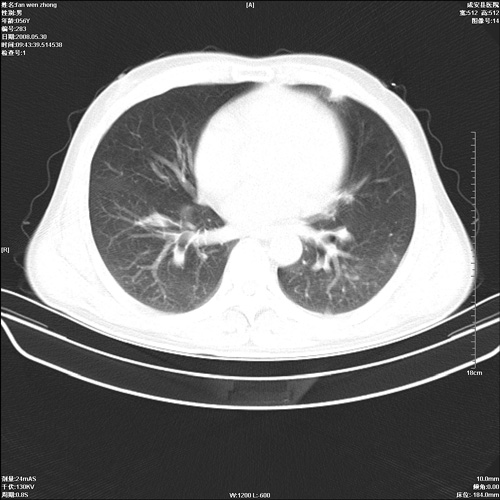

病人 男 56岁 一周前高热,体温达39-40度,经抗炎治疗后,体温渐降,达37,5-38度,轻微咳嗽,胸部不适 查白细胞为1.3万 行ct检查,请分析。

双肺内可见多发结节状病灶,并见小空洞,病人高热,白血球增高,应该是典型的迁徙性肺脓肿(多为金黄色葡萄球菌感染)。查一下口腔等其它部位有无感染灶。

双肺内可见多发结节状病灶,并见小空洞,病人高热,白血球增高,应该是典型的迁徙性肺脓肿(多为金黄色葡萄球菌感染)。建议治疗后复查.